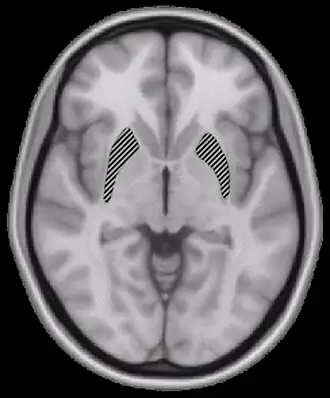

A degeneração cerebral é causada pelo próprio [HIV] e não por doenças oportunistas. As [vírus|proteínas virais] danificam as células nervosas diretamente ou através da infecção de células inflamatórias no [cérebro] e na [medula espinhal]. O HIV pode, em seguida, induzir essas células a danificar e desativar as células nervosas